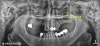

수술 전 엑스레이, 50대 여성 (2022.10)

처음 환자분의 뼈 상태입니다.

표시된 좌측 상악 부분에

임플란트를 심을 예정인데요.